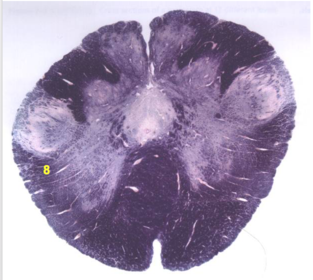

| Nucleus gracilis | |

| Nucleus cuneatus | |

| Fasciculus gracilis | |

| Fasciculus cuneatus | |

| Internal acruate fibers | |

| Lateral (external/accessory) cuneate nucleus | |

| Medullary pyramids | |

| Hypoglossal nucleus | |

| Hypoglossal nerve | |

| Dorsal motor nucleus of X | |

| Nucleus ambiguus | |

| Solitary tract | |

| Solitary nucleus | |

| ALS | |

| Medial lemniscus | |

| Medial longitudinal fasciculus | |

| Spinal tract of V | |

| Spinal nucleus of V | |

| Lateral (external, accessory) cuneate nucleus | |